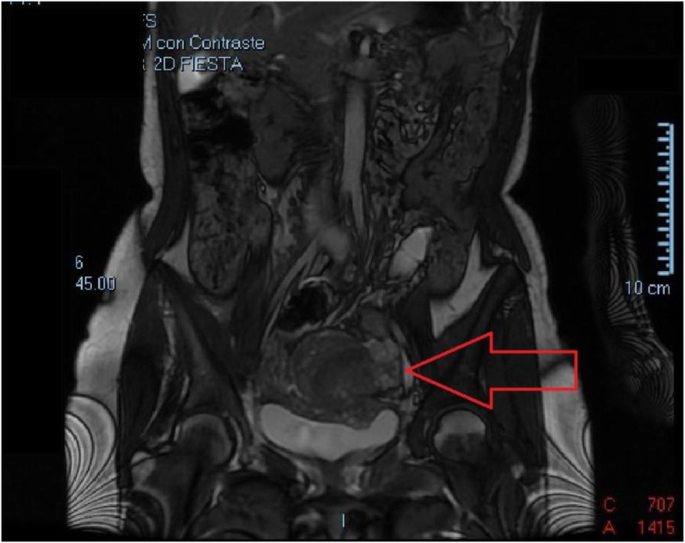

A 44yearold woman, known to have uterine fibroids, admitted with acute abdominal pain and vaginal bleeding Axial T2W (A) and T1W (B) MRI images show a heterogeneous mass (arrow) within the endometrial cavity The mass shows peripheral high signal (arrowheads) on the T1W image, due to hemorrhageOccasionally, a pedunculated endometrial fibroid may look like a completely intraluminal polypoid filling defect Mural tumors that reach several centimeters in size may distort the endometrial cavity in a variety of bizarre configurations Adnexal masses are lumps that form in the adnexa of the uterus, which includes the uterus, ovaries, and fallopian tubes Keep reading to learn more